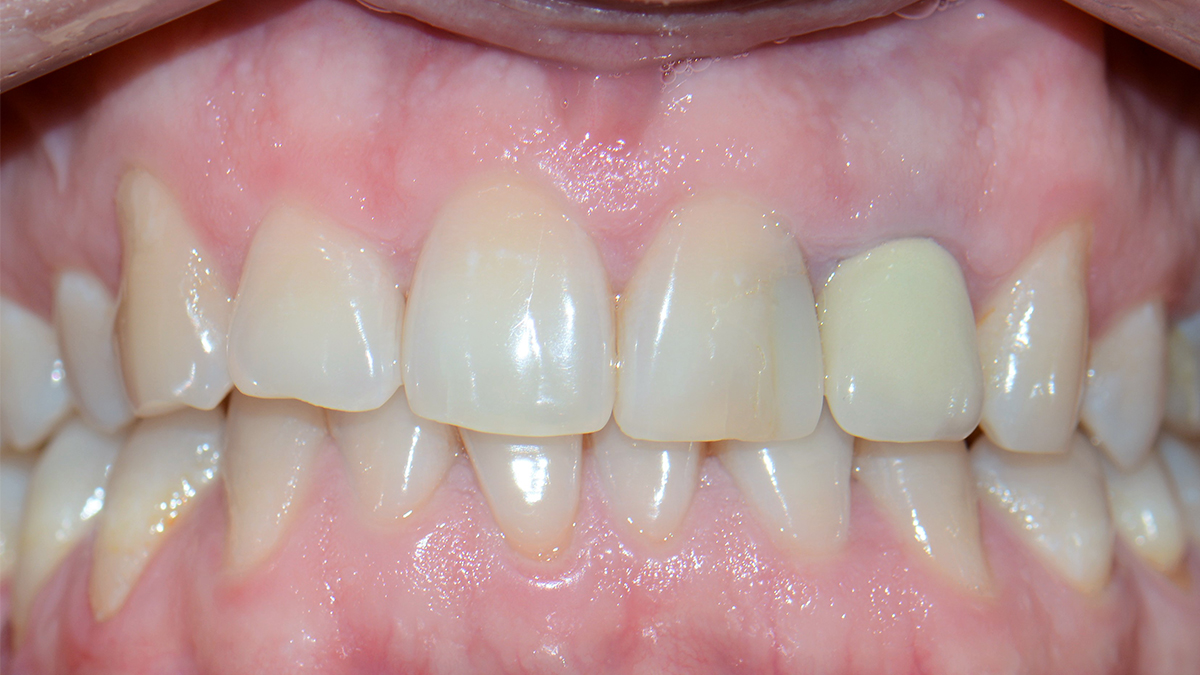

Általában ha a fognak csak egy kisebb része szuvas, a hiányzó rész kitisztítás után tömőanyaggal pótolható. A töméskészítést helyi érzéstelenítésben végezzük, egy alkalmat vesz igénybe. A tömőanyag egy speciális műanyag, kompozit, amely mind színében, mind fizikai tulajdonságaiban nagymértékben hasonlít a természetes foghoz, ezért alkalmas tartós és esztétikus tömések készítésére. Töméskészítés során a gyurmaszerű anyagot kis adagokban helyezzük az üregbe, majd az egyes rétegeket speciális lámpával világítjuk meg, melynek hatására megszilárdulnak. A tömés elkészültével az anyag kötése befejeződik, a fog terhelhető.

A tömőanyag tulajdonságaiból adódóan ma már, ha az üreg nem túl nagy, minden fogcsoport tömésére alkalmazható. Rágófogakban képes helyreállítani a funkciót, azaz egy erős, a rágóerőkkel szemben ellenálló tömés készíthető, frontfogakba (metszőfogak) pedig készülhet olyan esztétikus, észrevehetetlen tömés, mely kedvezően befolyásolhatja megjelenésünket, arckarakterünket.